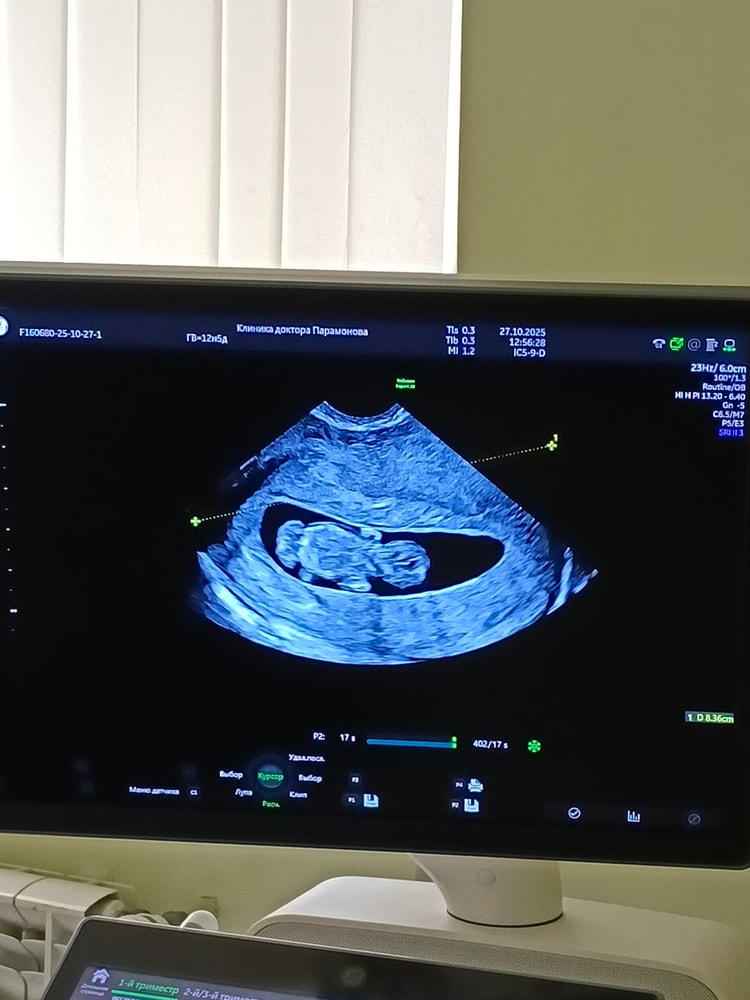

УЗИ на 11 неделе

Анализы, скринингиДевочки, это нормально, что расположение такое? Или это такой ракурс? 10.6 недель по ктр

Нормально ли, что он лежит горизонтально?

Если Вы об этом, то да, нормально :)

Анжелика , да, об этом) спасибо, врач хотела, чтобы было красиво, сказала непоседа, не лежит нормально и тут у меня закралось сомнение, нормально ли это, что он так лежит

Это норма, что они пока в горизонтальном предлежании)

Сроки пока маленькие)

Анжелика , у вас немного по-другому, а у меня прям спинкой получается, а вот то, что за ножками, я так понимаю, это жёлтый мешок?

Да, может быть ЖМ. В скором времени он исчезнет.